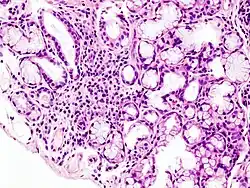

Das Sjögren-Syndrom kann – wie auch andere Kollagenosen – im Blut zum Abfall verschiedener Zellreihen sowie zu hohen Antinukleären-Antikörper-Werten (ANA) oder Rheumafaktor führen. Durch die Entzündung kommt es zum Anstieg der Blutkörperchensenkungsgeschwindigkeit (BSG) und des C-reaktiven Proteins (CRP). Als unspezifisches Zeichen kann es auch zu Leukopenie, Anämie und Thrombozytopenie kommen.[13] Spezifisch sind aber ss-A- und ss-B-Autoantikörper bei bis zu 70 % der Patienten sowie manchmal Antikörper gegen Epithelzellen der Ausführungsgänge der Speicheldrüsen. Zur Diagnosesicherung kann eine Biopsie von der Lippeninnenseite entnommen werden. In dem Bioptat ist eine Drüsenentzündung mit Lymphozyteninfiltration zu sehen.